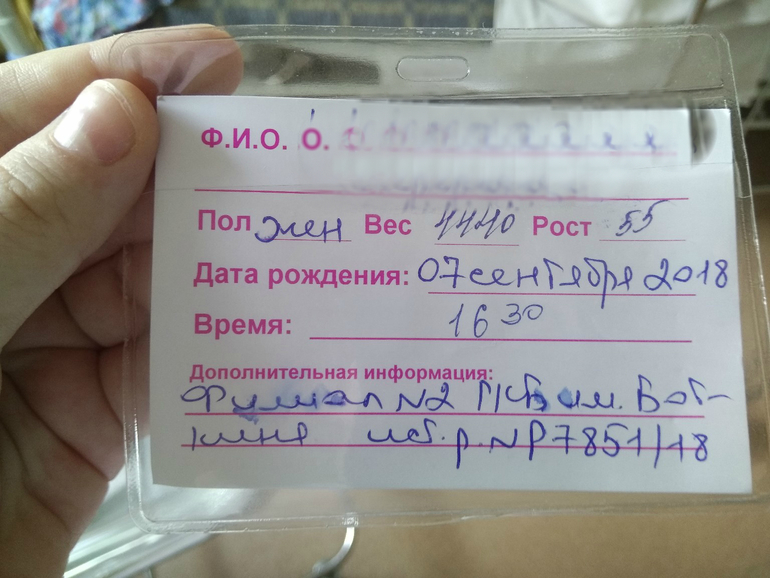

Родились мы в 16:30, 7 сентября, 4440 грамм, 55 см. Роды 16,5 часов. Моя тыковка!